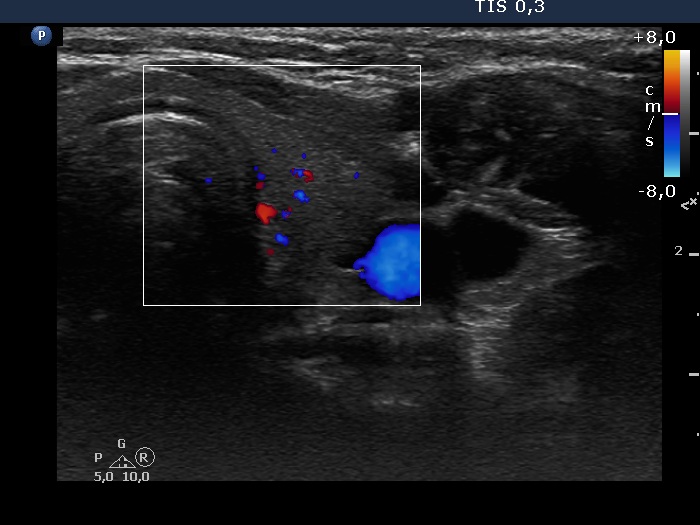

Consecutive patients with the final diagnosis of Hashimoto's thyroiditis - case 8 (659) (ultrasonographic picture 6)

Left lobe, longitudinal scan, color Doppler mode. The vascularization is average.